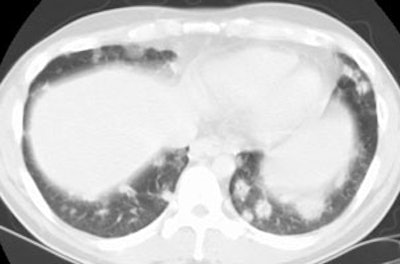

BOOP presenting with pulmonary nodules:

The patient below presented with complaints of cough, malaise, and a low-grade fever. The chest radiograph revealed some patchy left lower lobe airspace disease and vague nodular shadows- particularly in the lower lung zones. A chest CT was performed and demonstrated multiple nodular airspace abnormalities with variable margins. The lesions did not improve despite antibiotic therapy and all cultures were negative. Click images to enlarge. |

Open lung biopsy confirmed the diagnosis of BOOP. Following institution of therapy with steroids the lung lesions resolved. Click images to enlarge.